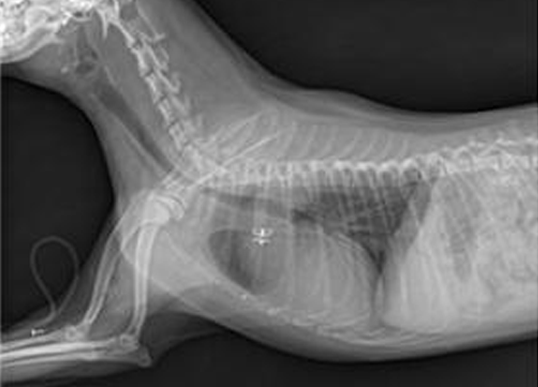

진단을 위해 기본적으로 각종 정밀 혈액검사와 요검사, 방사선검사, 초음파, 내시경 등을 실시하게 되며 치료는 진단된 질병을 바탕으로 약물 치료를 기본으로 하며 관리가 어려운 신장질환의 경우 혈액 투석을 실시하고 있습니다.

증상 치료 이첨판 폐쇄 부전증, 삼첨판 폐쇄 부전증, 폐동맥 고혈압,동맥관 개존증, 부정맥, 폐수종 흉부 방사선 검사, 심전도 검사, 심장초음파 검사, 혈관 조영술,동맥관 개존증 폐쇄술, 심장 박동기 장착

증상 치료 폐렴, 기관/기관지염, 기관협착, 기관지 협착, 고양이 천식 흉부 방사선 검사, 투시 검사, 관련 샘플 및 배양검사, 호흡기 종양 세포 흡인 검사